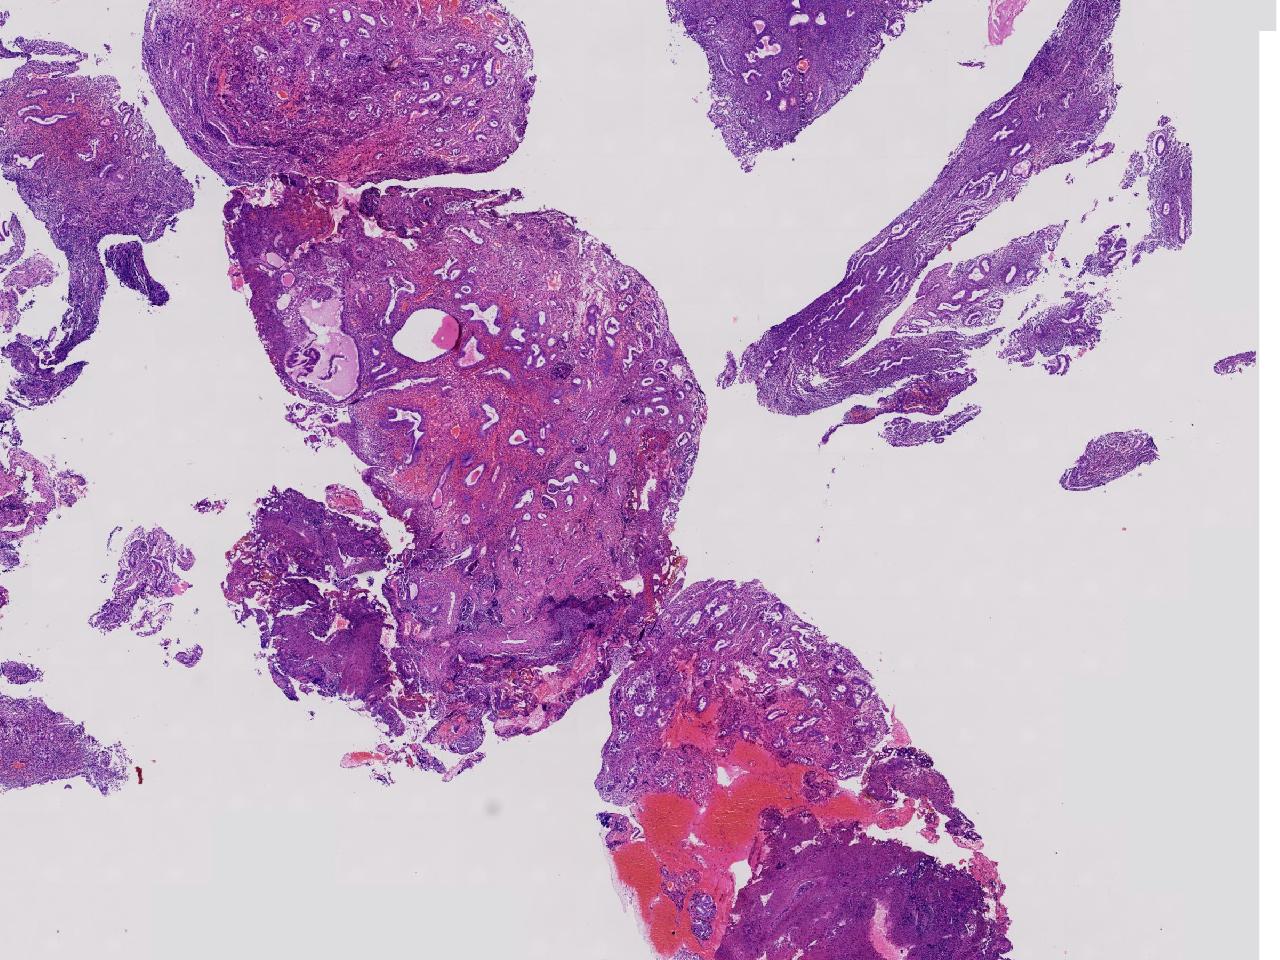

性别

女

年龄

55岁

女,55岁,月经紊乱4年,彩超示:子宫内膜增厚(内膜厚15.7mm),末次月经:2025年7月27日。

标本名称

宫腔镜下子宫内膜活检

大体所见

灰粉色不整形软组织多块,1.5X0.8X0.6厘米。

考虑:子宫内膜增生伴子宫内膜炎

子宫内膜增生紊乱,内膜息肉样结构